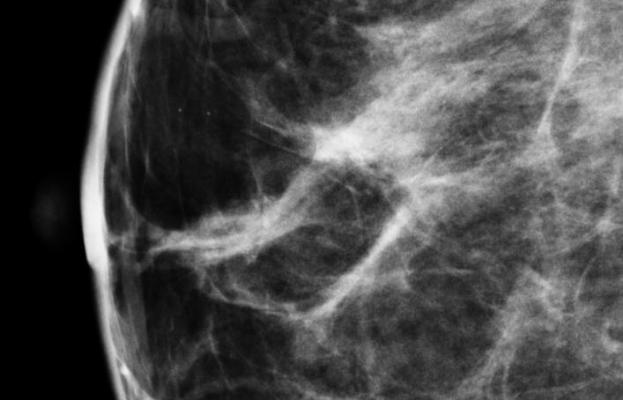

Virginia has amended its breast density inform law to include language in information given to patients explaining the risk of dense breast tissue.

Originally signed into law by Gov. Bob McDonnell in 2012, the amendment strengthens the density notification to women and is modeled after laws in New York and California. The amendment to the law becomes effective July 1, 2013.